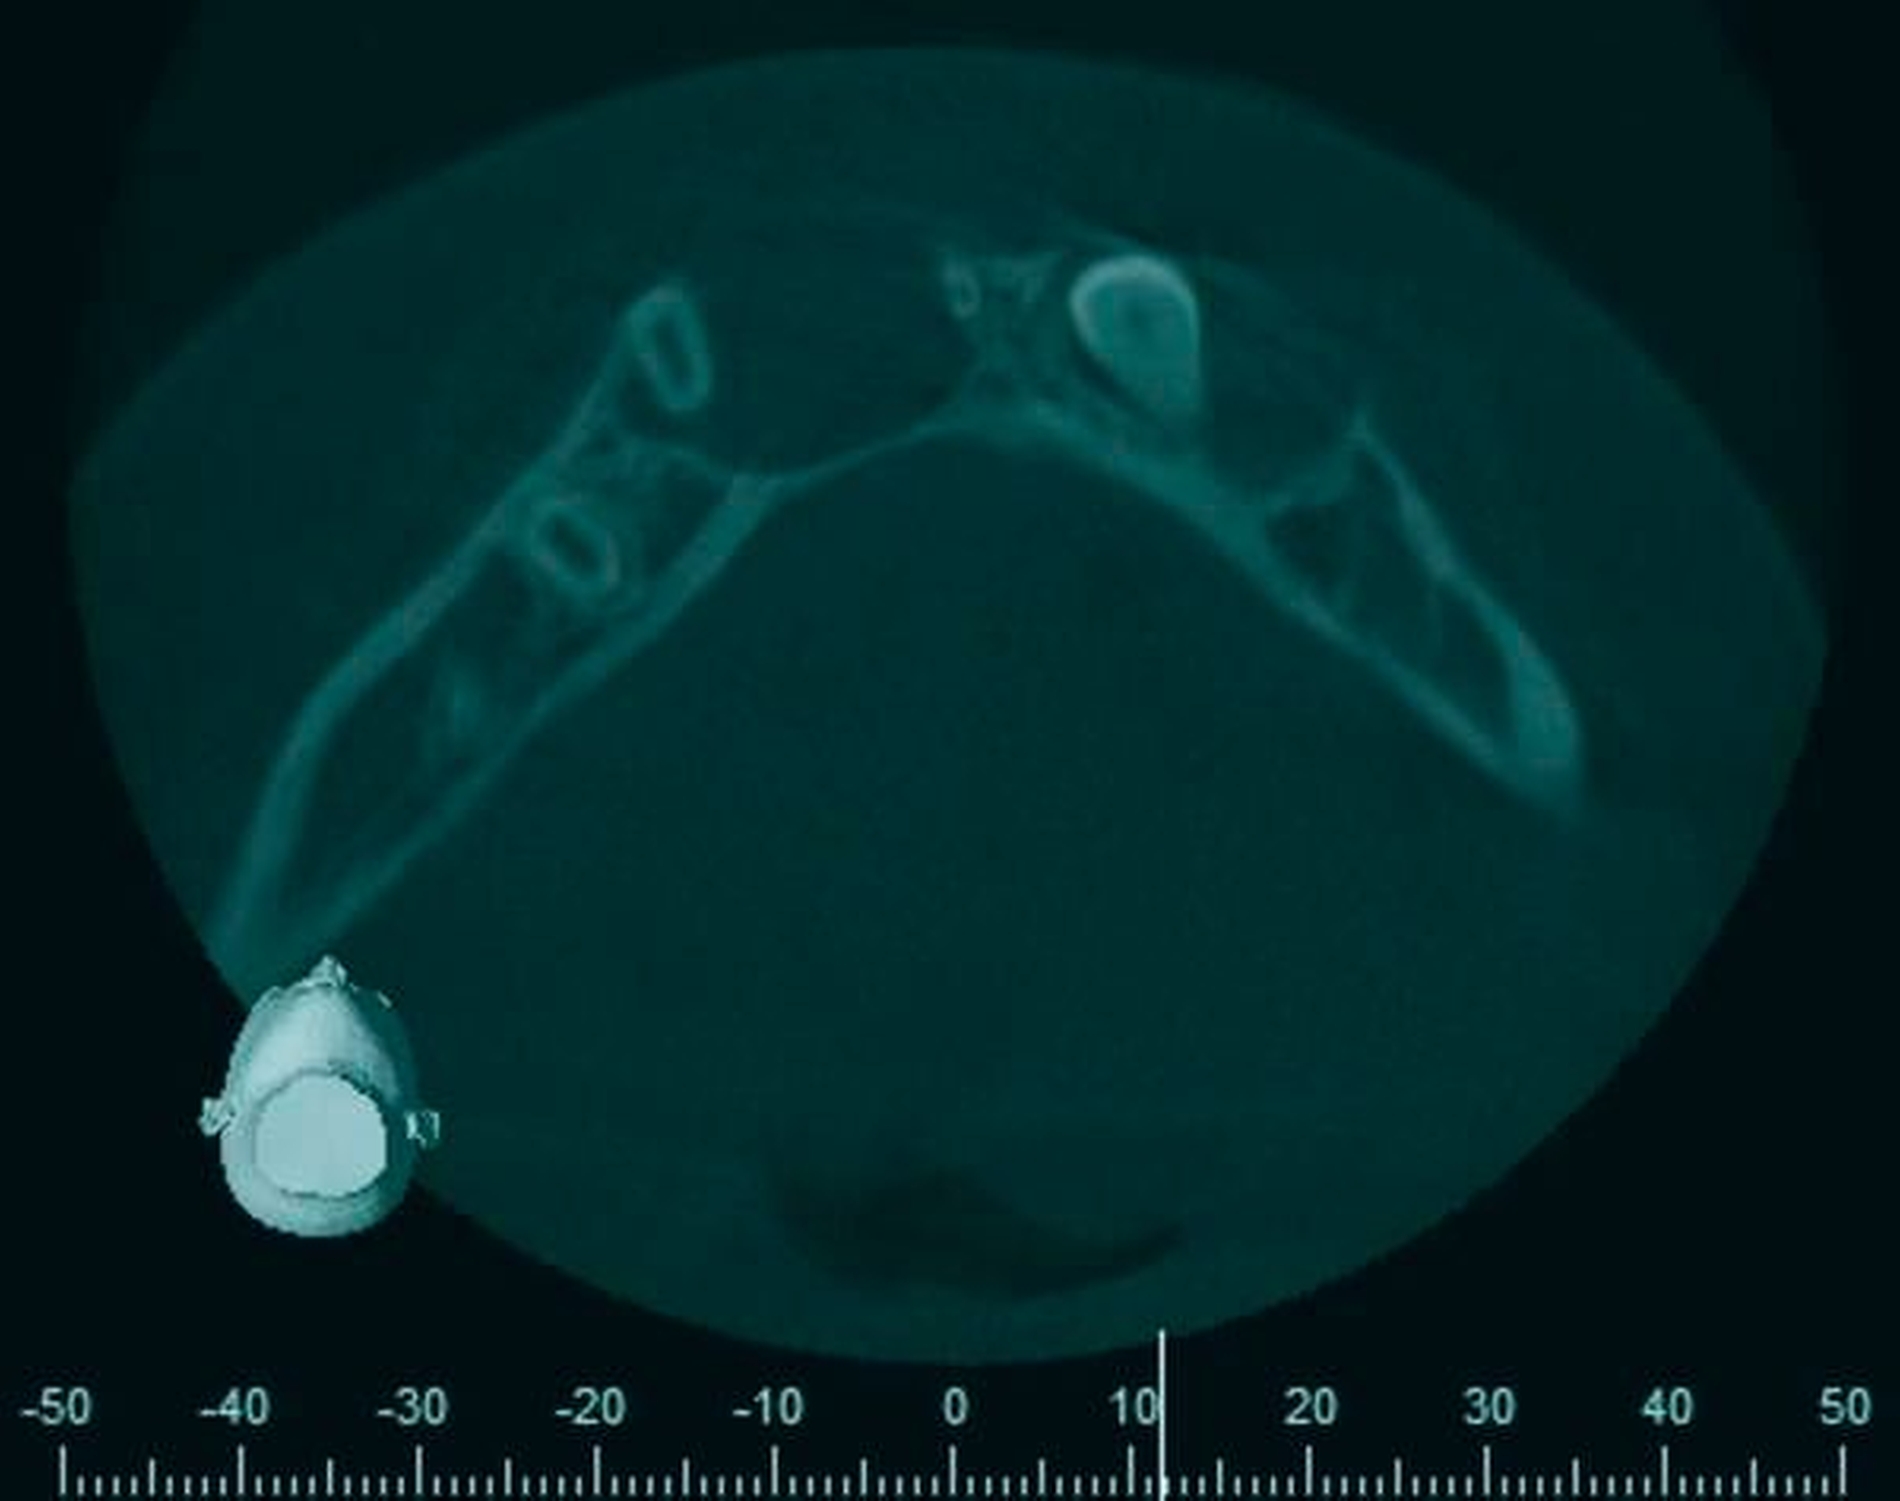

Radiologischer Befund

Im OPG (Abbildung 1) sowie in der DVT (Abbildungen 2 bis 5) imponieren zwei scharf begrenzte osteolytische Befunde im Bereich der anterioren Mandibula regio 34–32 und 41–43. Der retinierte Zahn 33 liegt basal im Lumen der Aufhellung.

Eine dreidimensionale Bildgebung zur Evaluation der Ausdehnung des Befunds und zur möglichen Beteiligung von Nachbarstrukturen ist sinnvoll. Hierfür sind DVT oder CT im Niedrigdosisprotokoll geeignet.